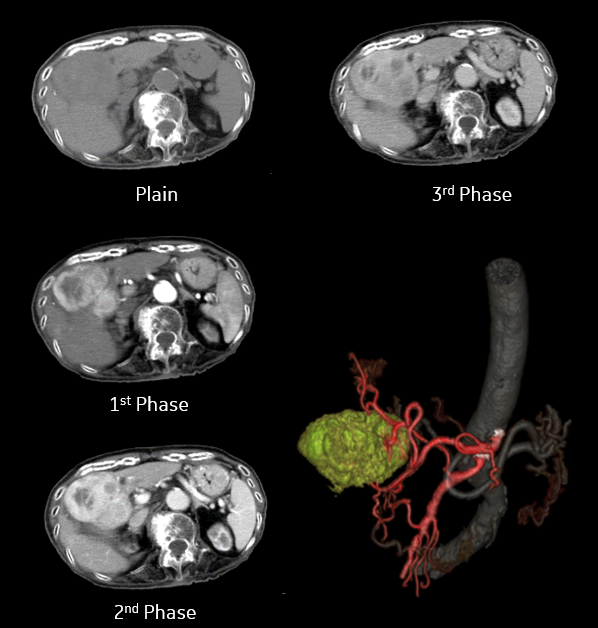

膵臓病変

消化器領域において膵臓病変は見つけにくいと言われていますが、ある患者様でエコーでは映らなかった膵臓がんをRevolution ACTで見つけることができました。 [画像①] デジタル検出器による感度向上とノイズ抑制の画像再構成方法(ASiR)により高画質な画像と感じます。

actcv_sakamoto_naika_02_big.png

[画像①] 膵臓がん